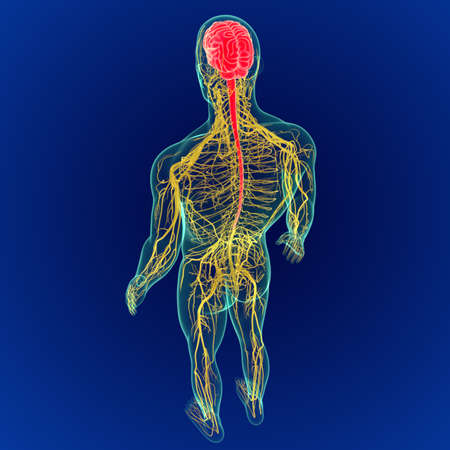

3D Illustration Concept of Central Organ of Human Nervous System Brain Anatomy

Illustrating the role of the central nervous system in processing sensory information and coordinating motor responses.

A captivating digital depiction of the human nervous system, highlighting the brain and spinal cord with glowing neural connections, perfect for educational materials.

Detailed anatomical illustration showing the human brain, spine, and nervous system with a focus on the intricate connections between them

An Electro stimulation digital illustration of human nervous system, highlighting brain and spinal cord with glowing nerve pathways

Vivid visualization of the human nervous system, highlighting brain and spine against dark blue background